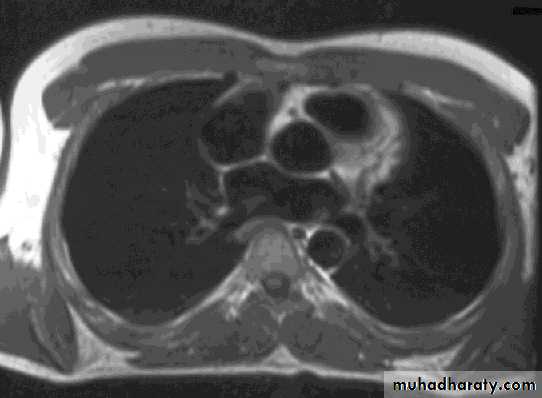

ComparisonsMRI image

CAT image

thorax

Compare bone and soft tissue density